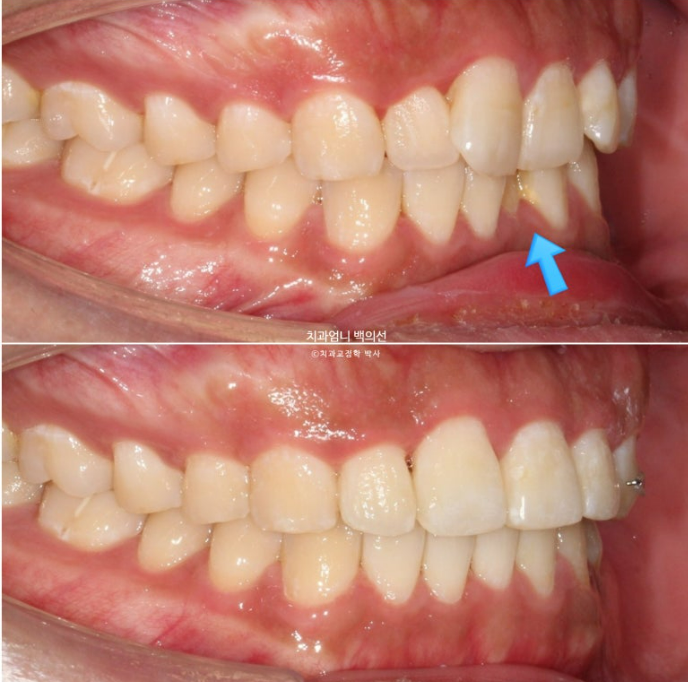

위가 치료 전 아래가 치료 후 예상 시뮬레이션 입니다.

파란 화살표 부위의 비스듬히 마모된 부분이 교정 전에는 티가 안나다가 배열이 완료가 되면 비로소 티가 많이 나게 되는거죠.

이런 경우 마모된 부분을 레진으로 수복하기 보다는 티가 덜나게끔 끝단을 조금 편평하게 다듬으면 좋습니다.

MTA 부분교정을 제1소구치부터 제1소구치까지 위 아래 8개씩 부착하여 치료를 시작했습니다.

치료시작 4개월째 모습입니다.

배열이 거의 완료되었습니다.